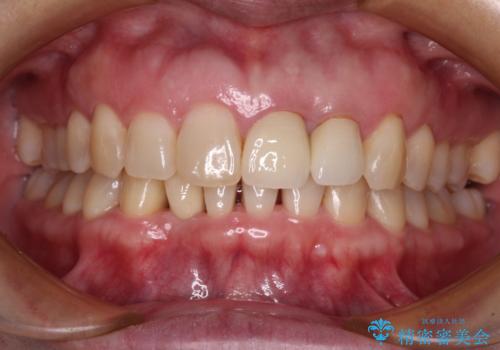

前歯のでこぼこをスッキリと 目立たない装置による抜歯矯正

治療開始直後は、あっという間に歯列が整い、すぐに終わるのではないかと思われましたが、治療の後半においては抜歯したスペースがなかなか閉じきらず、当初予定していた2年以上の期間を要することとなりました。

周りの方からも整った歯列を羨ましいとおっしゃっていただけるようになり、患者様には大変満足していただきました。